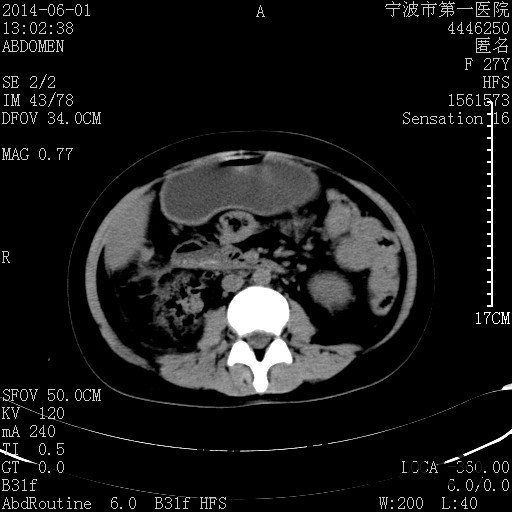

患者,女,27岁,因“右下腹疼痛伴呕吐2天”入院 患者无明显诱因出现右下腹疼痛伴呕吐、发热,体温最高39度,急诊CT示:右肾集气,考虑气性肾盂肾炎。

查体: 右肾区叩击痛,右下腹压痛,无反跳痛。 辅助检查: 空腹血糖9.7mmo/L,餐后血糖18mmol/L 血常规:白细胞 11.3*109/L, 中性百分比 77.4%, 血红蛋白 8g/L, 血小板 319*109/L 尿常规 WBC+++ 生化:白蛋白 37.5g/L,肝肾功能正常 泌尿系CT:右肾集气

诊断为“气性肾盂肾炎,感染性休克,糖尿病酮症酸中毒” 血、尿、脓液培养均示“克雷伯杆菌” 入院第2天行“右双J管置入术” 入院第3天、7天行“右肾穿刺造瘘术” 入院1月行“右肾切除术” 术后顺利康复出院。